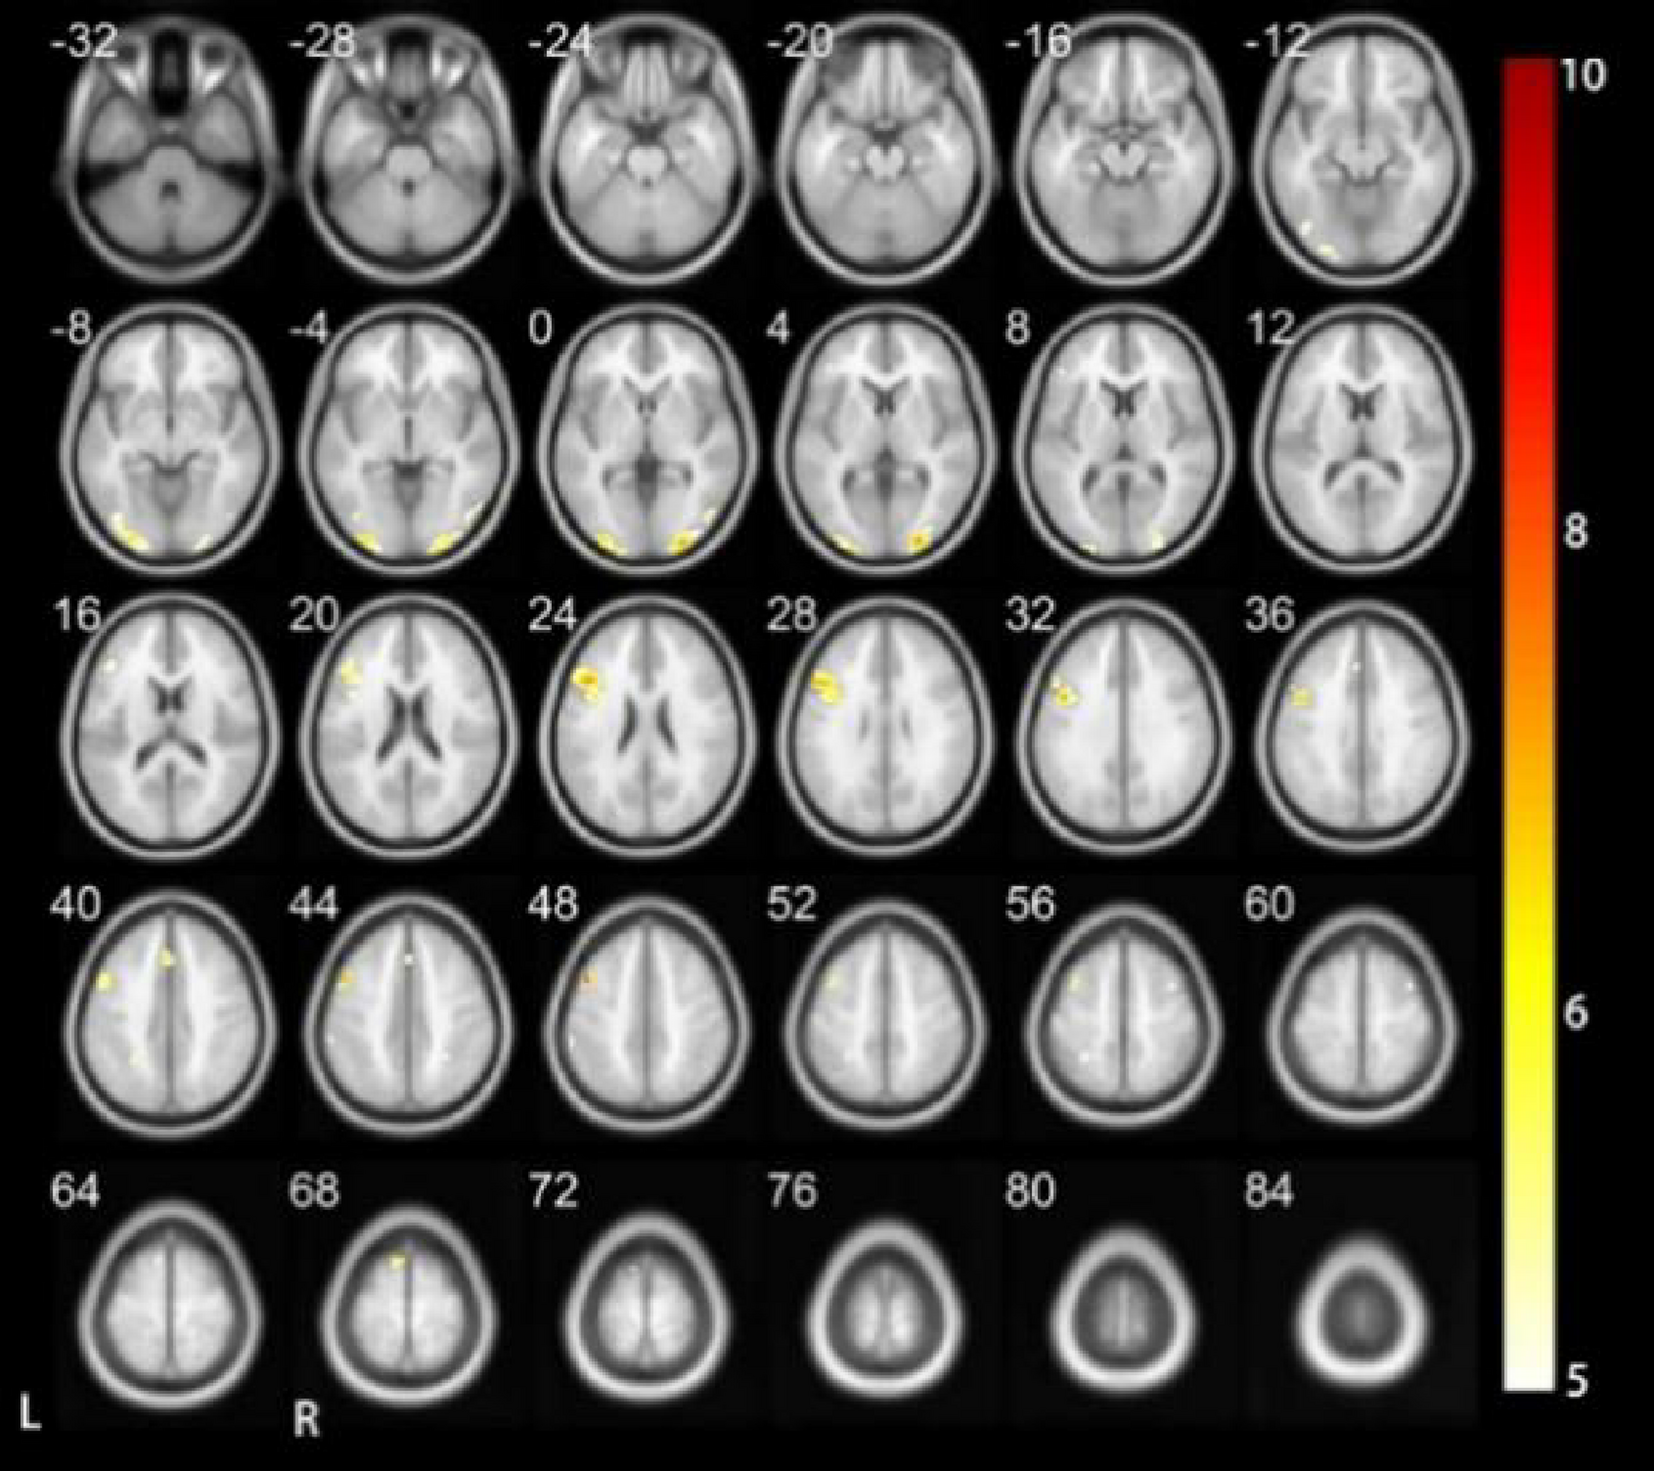

Results of executing vocal triple-time HC.

From: Preliminary study on the neural mechanisms of four tone recognition in deaf children using fMRI